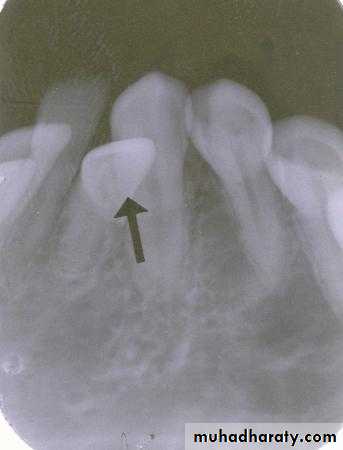

Is the composite restoration on tooth # 8 (arrows) located on the buccal or lingual?

canine filmincisor film

The restoration is located on the buccal. The tube head moves mesially from the canine film to the incisor film (x-ray beam projected more distally) and the composite moves distally, which is the opposite direction.